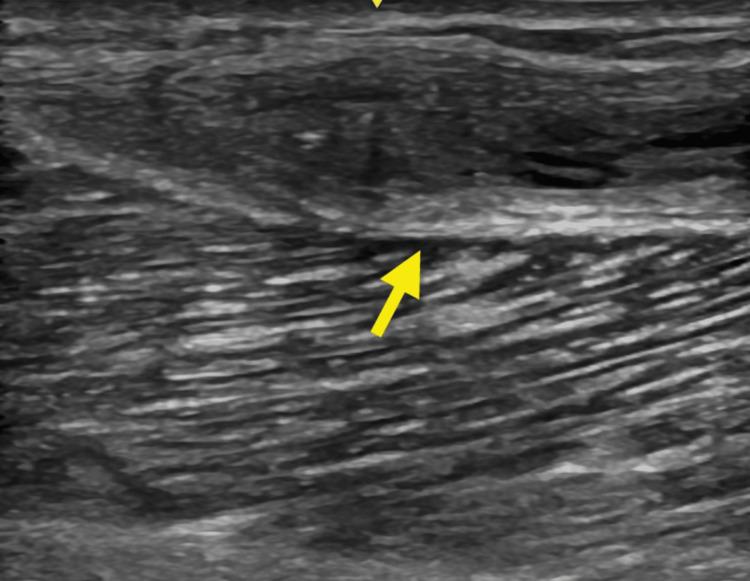

A 49-year-old man presented with repeated episodes of posterior knee effusions 11 months following right knee medial meniscus debridement. He was referred to Physical Medicine & Rehabilitation (PM&R) by his orthopaedic surgeon for further non-operative management. He had previously undergone ipsilateral vein stripping procedures with vascular surgery five months following his meniscal procedure. Magnetic resonance imaging (MRI) of the knee with contrast along with a subsequent ultrasound evaluation with no evident power Doppler flow confirmed the presence of a right posterior-medial gastrocnemius fluid collection extending extramuscularly into the proximal one-third of the medial head of the gastrocnemius muscle. These imaging findings combined with the yellow-clear aspirate consistent with synovial fluid confirmed the presence of a Baker's cyst with unusually distal extramuscular extension and subcutaneous location just superficial to the medial head of the gastrocnemius muscle. Successful implementation of platelet-rich plasma (PRP) and doxycycline tissue sclerosis emphasized the key role that nonoperative modalities have in treating Baker's cysts. The patient continues to respond appropriately with resolution of his symptoms noted three weeks after his initial sclerotherapy session and an additional treatment performed with half the initial dose of doxycycline. This case demonstrates the successful treatment of a Baker's cyst with an unusually distal location.

一名49岁男性在右膝内侧半月板清创术后11个月出现反复的膝关节后方积液。他被骨科医生转诊至物理医学与康复科(PM&R)进行进一步的非手术治疗。他在半月板手术后五个月曾接受同侧血管外科的静脉剥脱手术。膝关节磁共振成像(MRI)增强扫描以及随后的超声检查(无明显的能量多普勒血流信号)证实右后内侧腓肠肌有液体积聚,且积液延伸至腓肠肌内侧头近端三分之一的肌外区域。这些影像学表现结合与滑液相符的黄清色抽出液,证实存在一个囊肿,该囊肿具有异常的远端肌外延伸且位于腓肠肌内侧头浅面的皮下,符合贝克囊肿的表现。富血小板血浆(PRP)和强力霉素组织硬化治疗的成功实施强调了非手术方式在治疗贝克囊肿中的关键作用。患者在首次硬化治疗后三周症状缓解,且使用初始剂量一半的强力霉素进行额外治疗后,症状持续得到改善。该病例展示了对一个位置异常偏远的贝克囊肿的成功治疗。